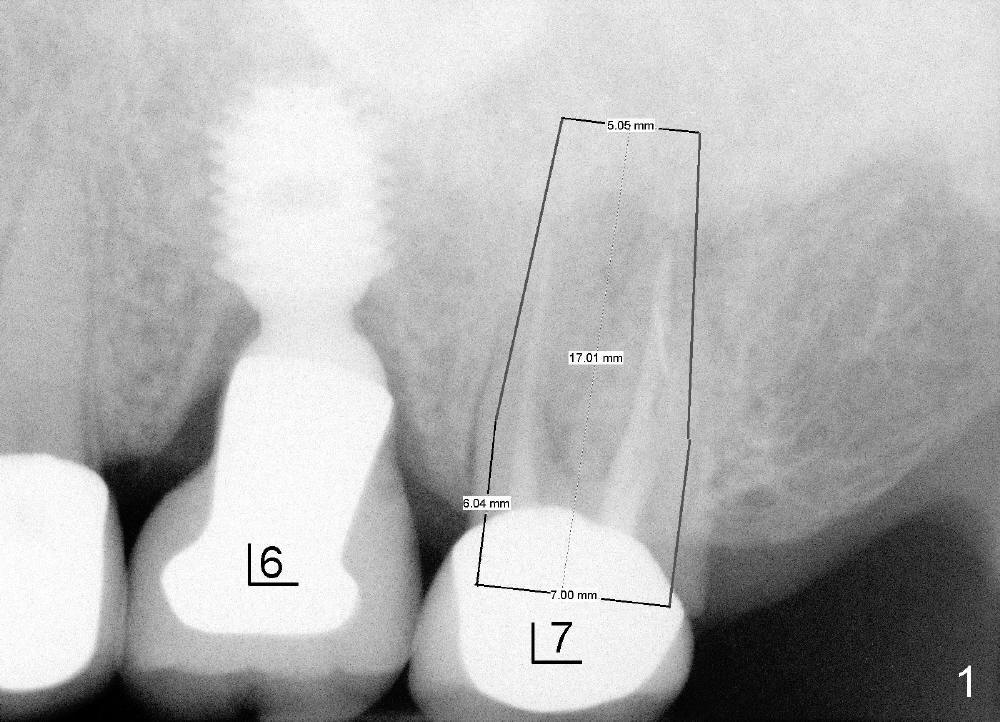

上颌磨牙有三个牙根,拔牙后一般有三个牙槽窝(图七(示意图)A:MB:近中颊侧;DB:远中颊侧;P:鄂侧),三个牙槽窝之间便是中隔(S)。如果中隔上面上颌窦不低,种植体应该种在中隔中。翁先生左上第二磨牙(图一:7)就与上颌窦无关,似乎后者不存在,前者牙根折裂,拔除后发现中隔鄂侧是一个斜坡,不容易插入圆骨凿或者钻头,所以用扁骨凿(图二)将中隔沿颊鄂侧劈开(图三),然后容易在中隔当中插入圆骨凿(图三插图白圆圈;图七B:蓝圆圈),由于中隔鄂侧阻力小,最后植牙(图七C:粉红色圆圈)不由自主地掉入鄂侧(图四),不得不移动颊侧粘骨膜瓣(图五B)关闭颊侧牙槽窝(图四插图(镜影观):MB;DB),图六镜影观(术后七天)显示种植体明显偏向鄂侧(P),可能造成以后修复困难。